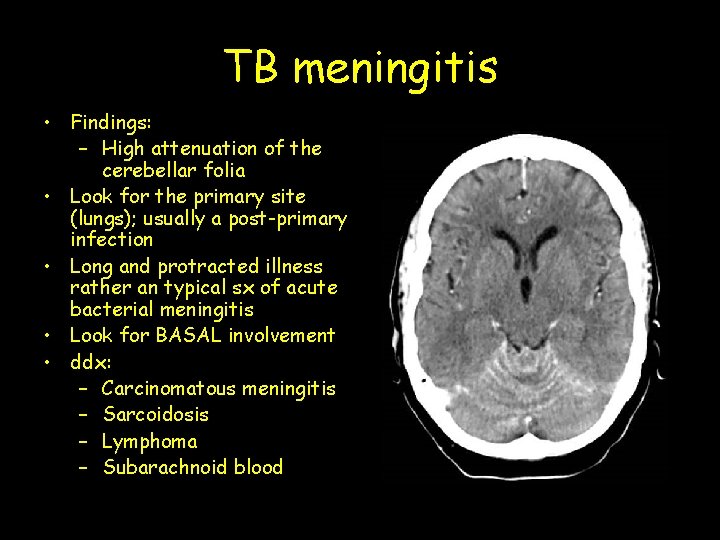

TB meningitis • Findings: – High attenuation of the cerebellar folia • Look for the primary site (lungs); usually a post-primary infection • Long and protracted illness rather an typical sx of acute bacterial meningitis • Look for BASAL involvement • ddx: – Carcinomatous meningitis – Sarcoidosis – Lymphoma – Subarachnoid blood